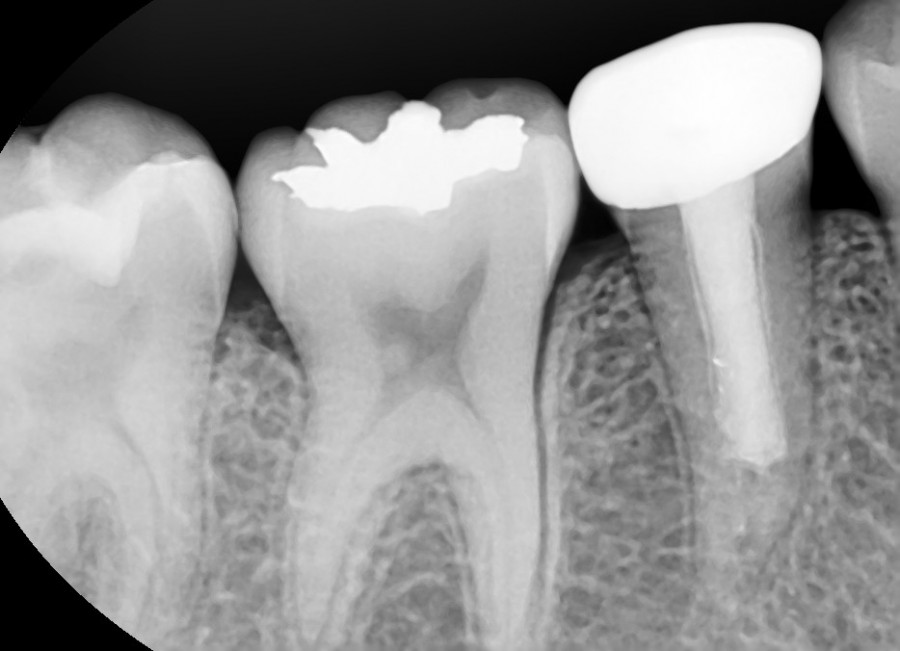

치수(신경)이 괴사되어 염증이 심한 상태로 내원한 14세 여환이었습니다. 뿌리도 다 성장하지 않은 상태였지만 MTA 신경치료를 통해 정상적인 길이로 뿌리가 성장하였고

온전히 기능하는 상태로 유지되고 있는 것을 보니 매우 다행이었습니다.